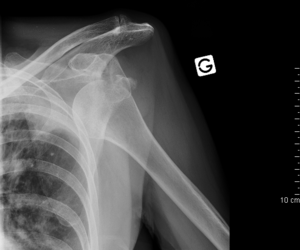

Anterior shoulder dislocation

- Shoulder dislocations account for 50% of all major joint dislocations, 90-98% are anterior[1]

- Arm held in abduction with shoulder lacking normal rounded contour

- Plain film X-ray of shoulder in at least 2 views (axillary lateral or scapular "Y" view important to show anterior vs posterior displacement of humeral head)

- Also need to rule out fracture-dislocation